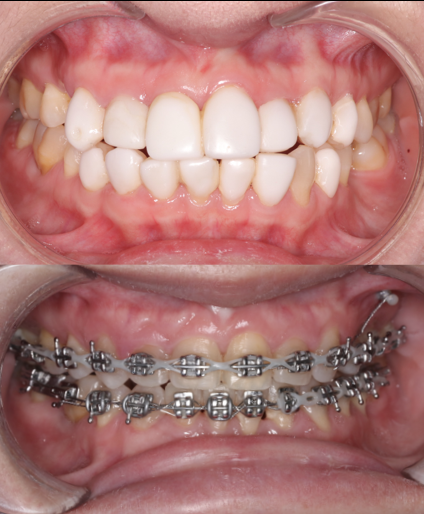

Before

After

BRACES - IMPACTED CANINE

This patient presented with an impacted upper right canine. Through precise orthodontic treatment, the tooth was successfully guided into its correct occlusal position. The full case was completed in just 16 months, resulting in a well-aligned, functional, and esthetically pleasing smile — expertly treated at Moral Dental Clinic.